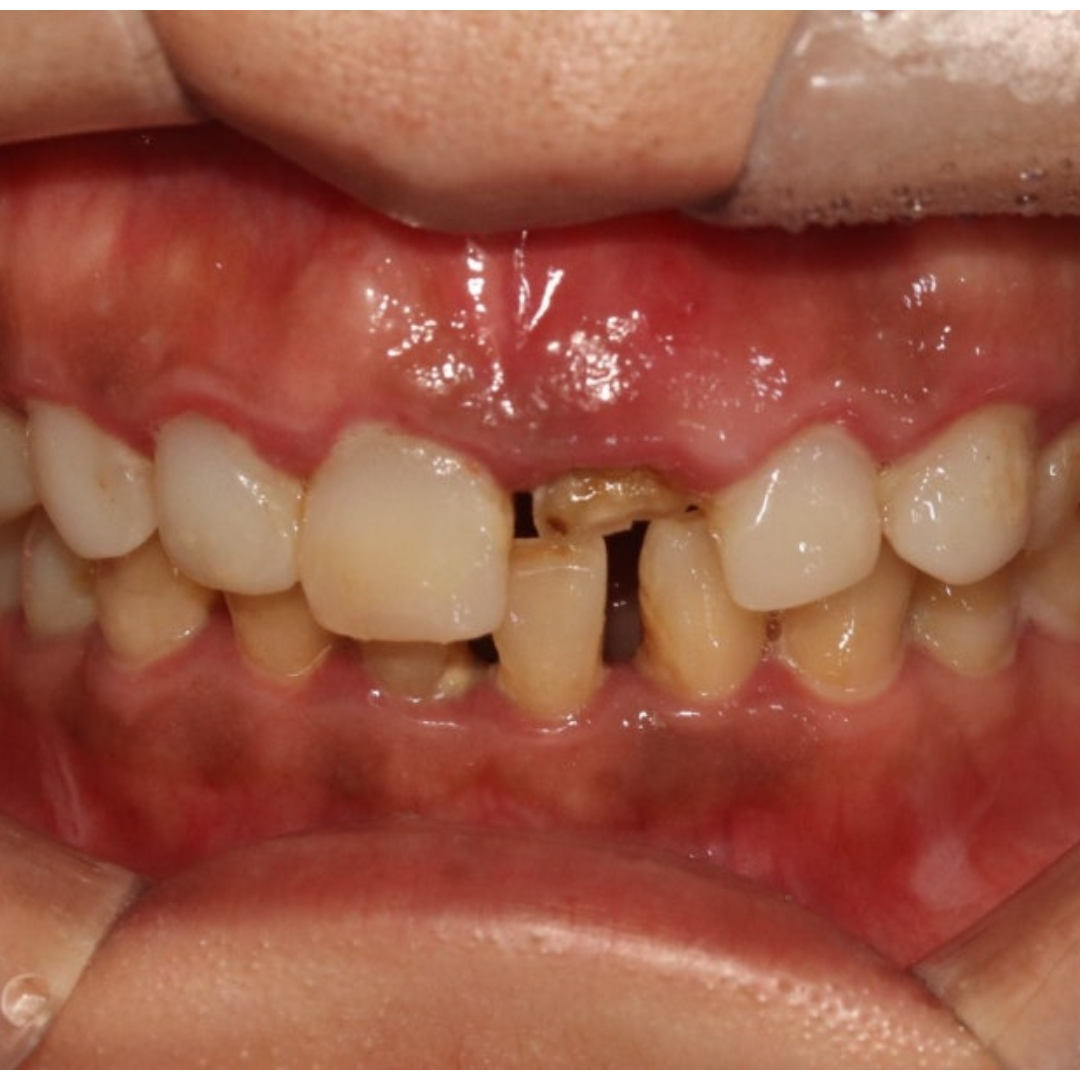

• 본 컬럼은 56조 제 1항의 의료법을 준수하여 작성되었으며 실제 내원 환자분의 동의하에 공개된 치료과정의 사진이 포함되어 있습니다.

개인에 따라 진료 및 치료방법이 다르게 적용될 수 있으며, 효과와 부작용이 다르게 나타날수 있는점을 안내 드립니다.